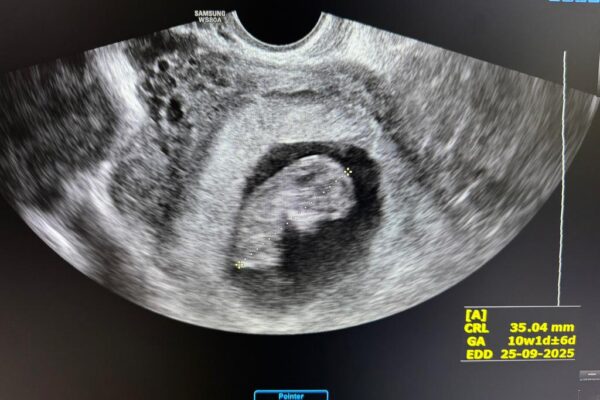

Пеш аз ҳомиладорӣ, дар саршавӣ ё дар давраи пайгирӣ — саволҳо дар бораи доруҳо, бемориҳо, парҳез ва назорати кӯдак одӣ мебошанд. Мо пайгирии мунтазам, ултрасадо ва машваратҳои эҳтиёткорона пешниҳод мекунем.

Маълумот пеш аз ҳомиладорӣ Пайгирии ҳомиладорӣ Ҳомиладории якчандгона